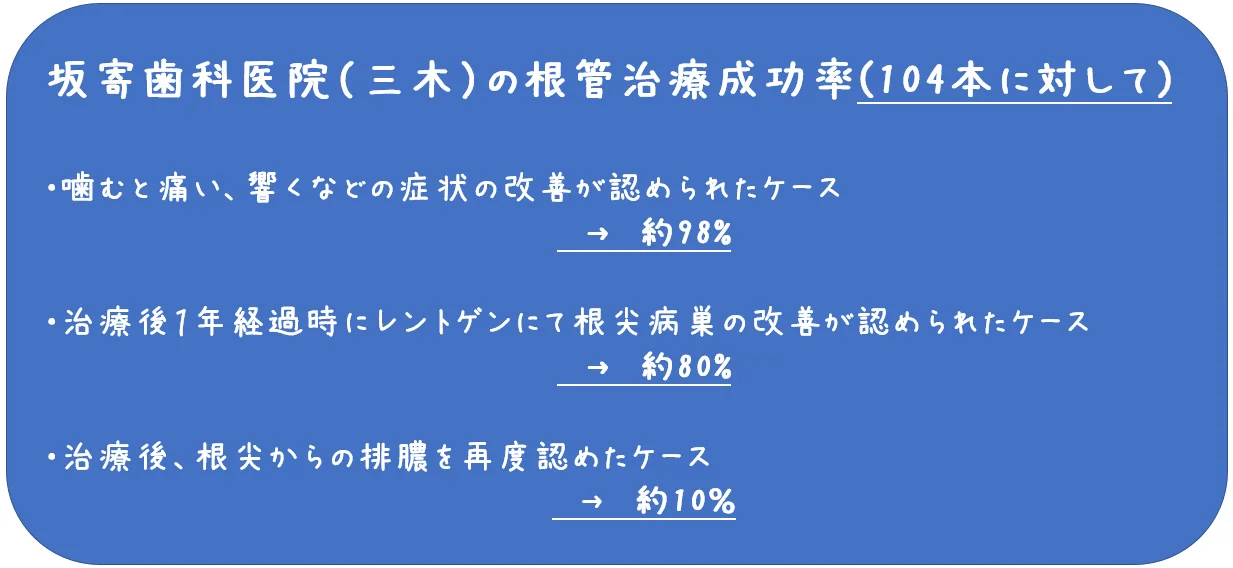

根管治療の成功率について

こんにちは。 なんか最近このHP・・・というかブログのアクセス数が急増しているんですが、なぜでしょう? どこかで晒されたんじゃなかろうかとハラハラしています(;'∀') まぁ歯チャンネルで顔出して回答しているので、今更なんですけどね。 さて…

続きを読む →